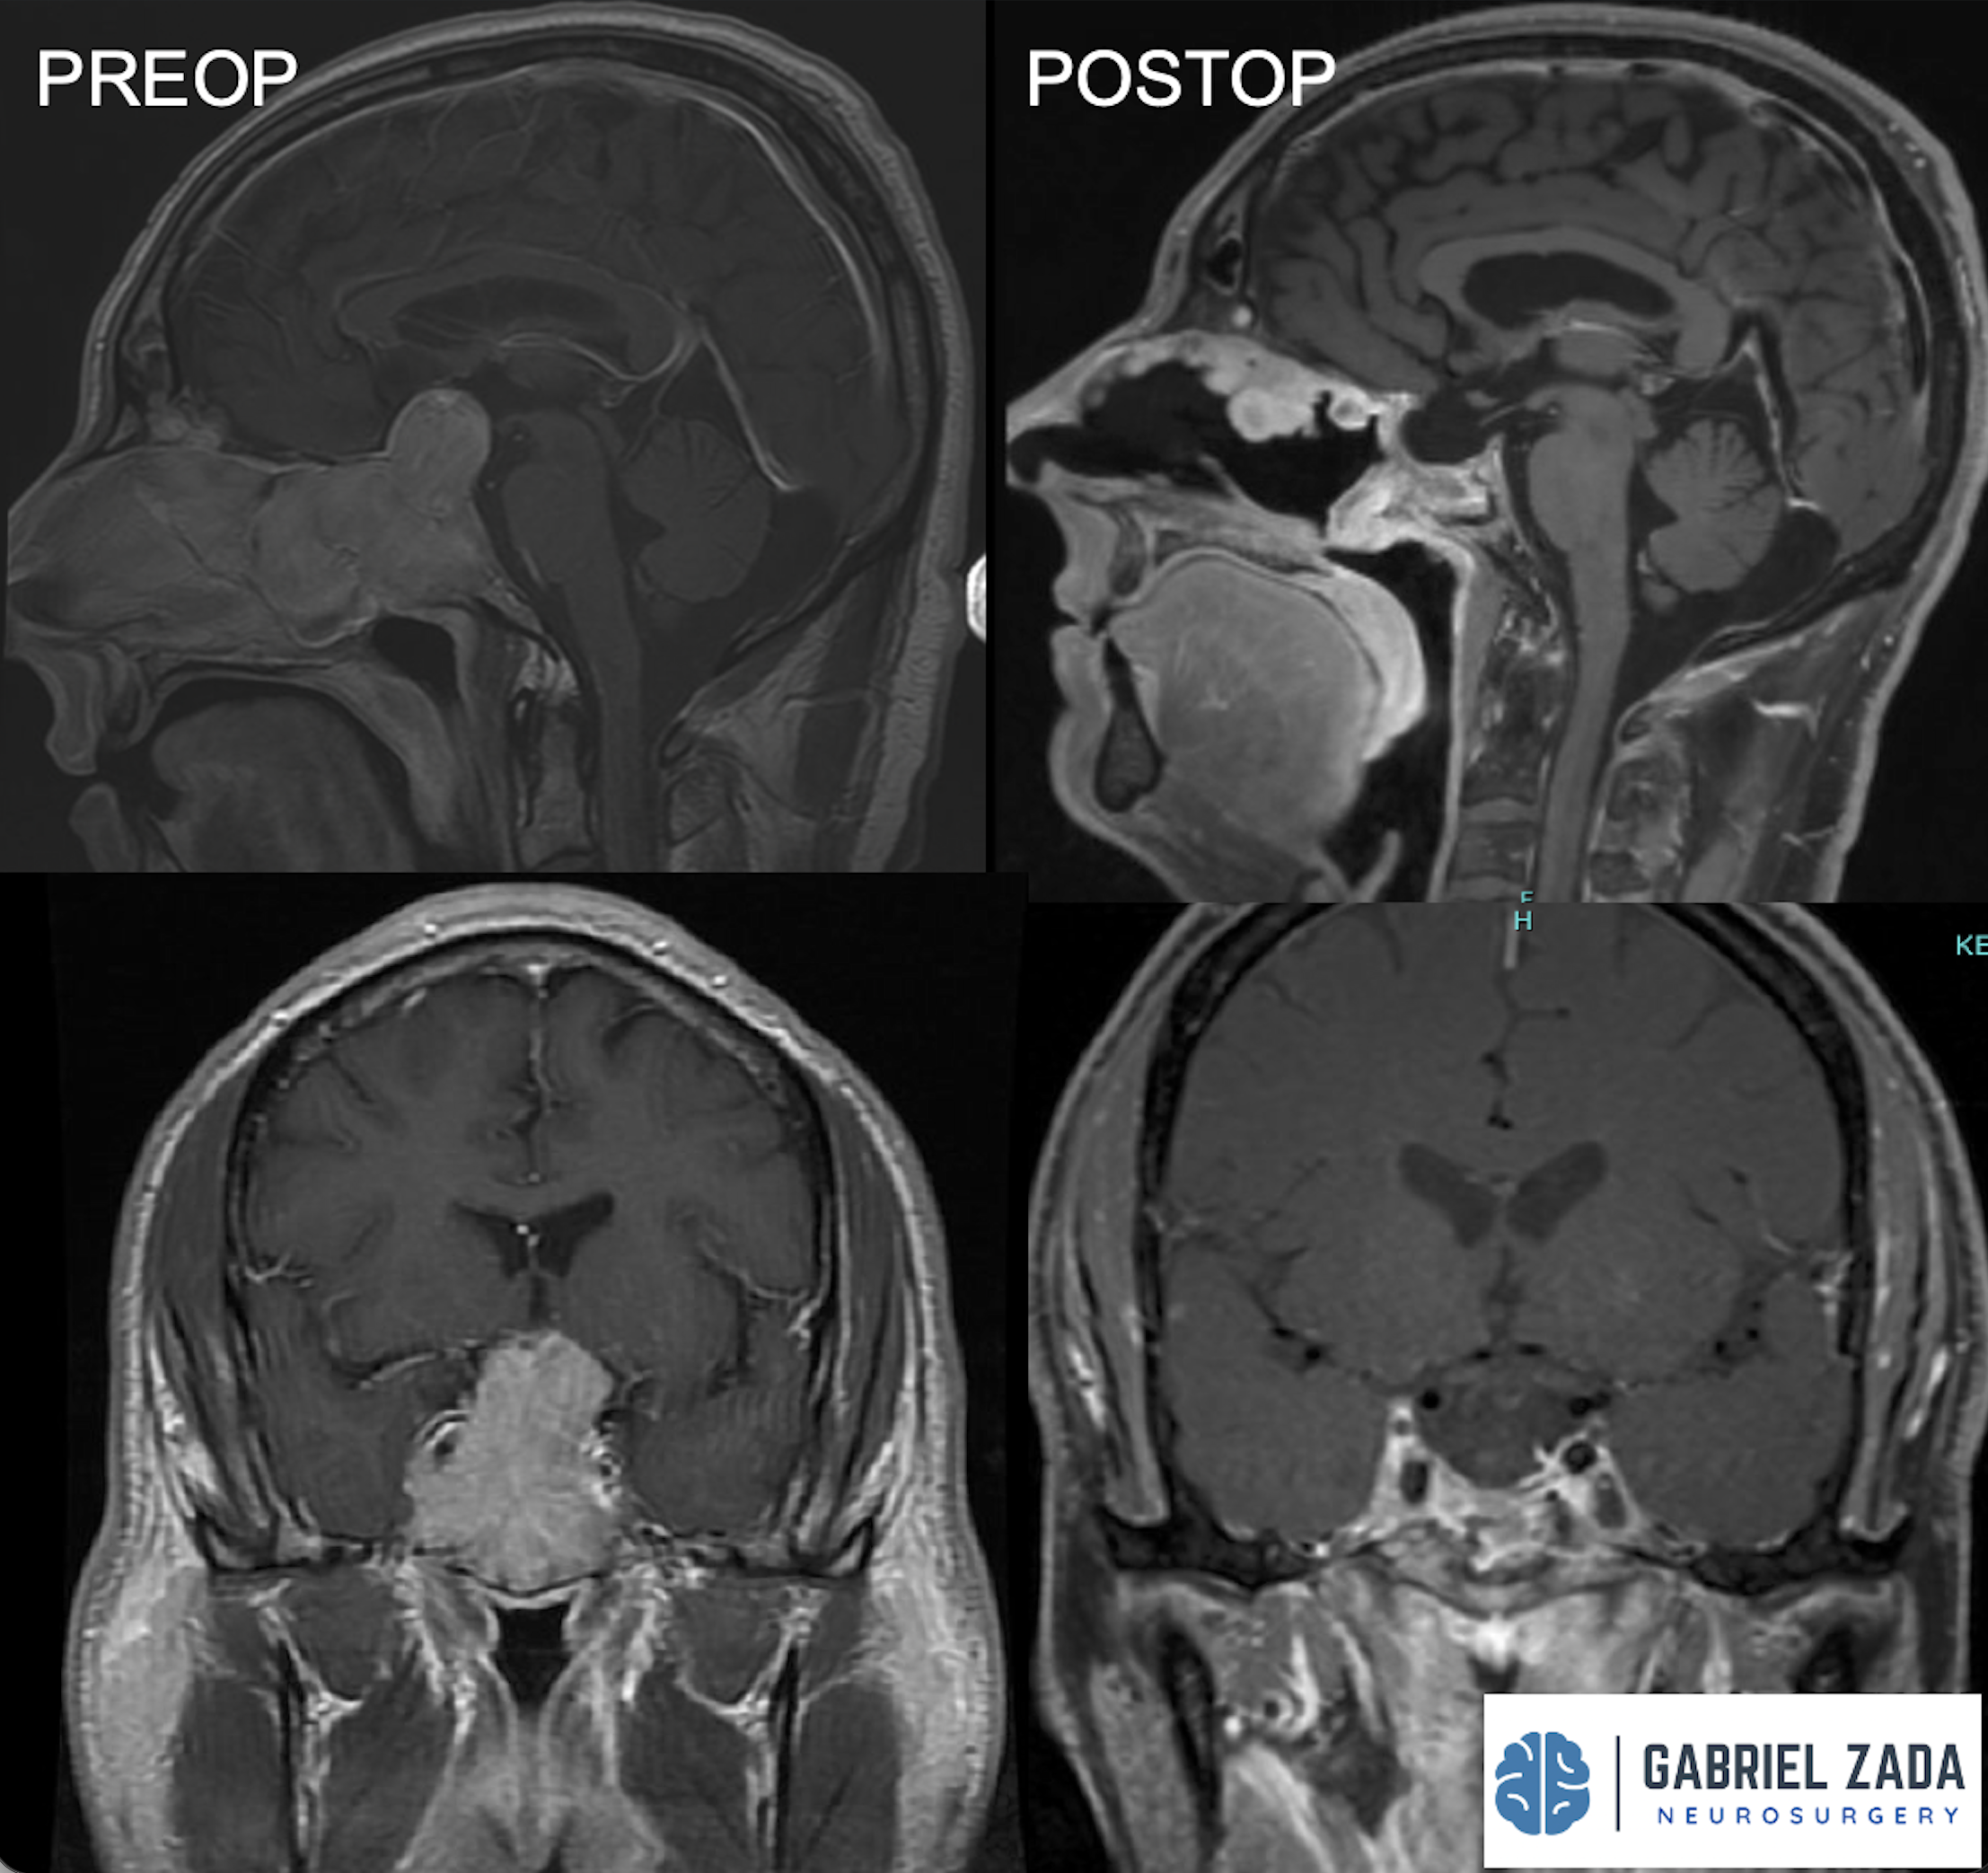

Explore this comprehensive gallery featuring pre‑ and post‑operative imaging of patients with skull‑base tumors treated by Gabriel Zada, MD, MS, FAANS, FACS. These cases highlight Dr. Zada’s expertise in advanced neurosurgical techniques and outcomes.

*Representative cases shown for educational purposes. All images de-identified. Individual results vary.